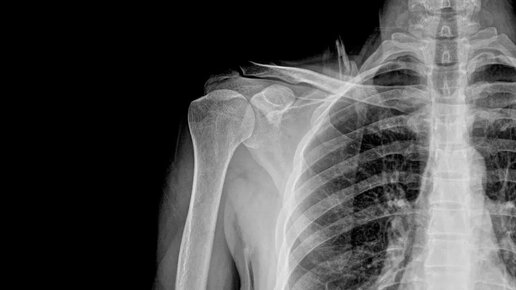

Рентгенологическое исследование органов грудной клетки

Рентгеновская диагностика позволяет исследовать практически все части тела и, конечно же, часто используется для оценки состояния легких. В этом случае делаются снимки в разных проекциях: Также проводятся жесткие снимки с передержкой для определения дополнительных деталей патологических изменений. Какие еще проводятся рентгеновские исследования? Можно выделить несколько...